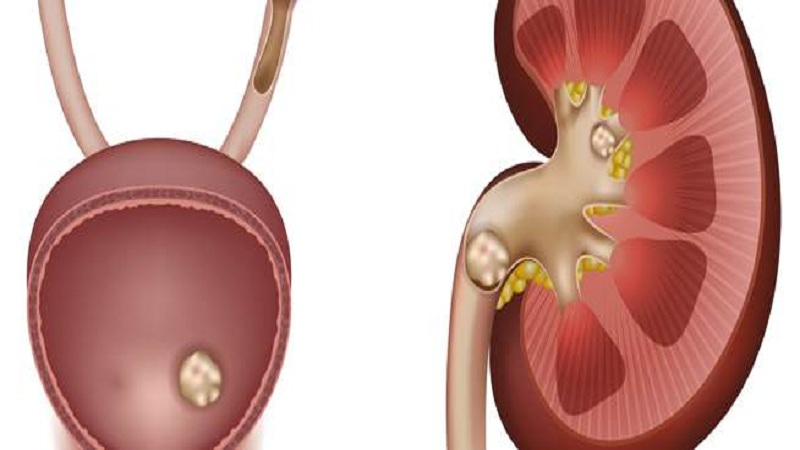

وكالات: كشف الطبيب الروسي، ألكسندر مياسنيكوف، عن مواد غذائية يؤدي تناولها بانتظام إلى تكون الحصى في الكلى.

ويشير مياسنيكوف، إلى أنه يجب تجنب الإفراط بتناول الأطعمة الغنية بالدهون الحيوانية، مثل اللحوم، وكذلك الملح والسكر، لأنها تساهم في تكون حصى الكالسيوم.

وتابع، أن "عصير الجريب فروت مادة غذائية ممتازة، ولكنها تزيد من خطر تكون الحصى، وكذلك فيتامين C عند تناوله بجرعات كبيرة"، موضحًا أن تناول أقراص الكالسيوم يعمل على تكون الحصى في الكلى.